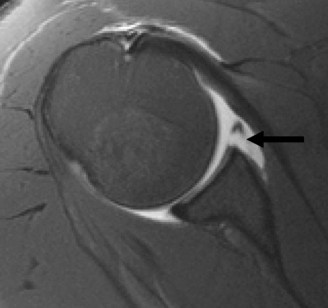

A 45-year-old carpenter presents with shoulder pain that has been ongoing for the last 3 months. He denies any significant injury. He describes night pain and significant discomfort at work. His imaging is shown in Figure 2–9. What is the most likely diagnosis?

Figure 2–9_From Shi LL, Mullen MG, Freehill MT, et al. Accuracy of Long Head of the Biceps Subluxation as a Predictor for Subscapularis Tears. _Arthroscopy 2015;32(4):615–619.

Discussion

The correct answer is (A). Medial subluxation of the biceps tendon as seen in this MRI is commonly associated with a tear of the subscapularis tendon which attaches to the lesser tuberosity. This patient’s pain may in part be attributable to the subscapular tear and this should be evaluated for during physical examination. Supraspinatus tears (Answer B) cannot be easily visualized on axial views and are not associated with medial biceps subluxations. A labral tear and ALPSA lesion (Answers C and D) are not seen on the images provided. The question stem and MRI are not suggestive of shoulder instability (Answer E). Objectives: Did you learn...? Diagnose and treat acute rotator cuff tears?